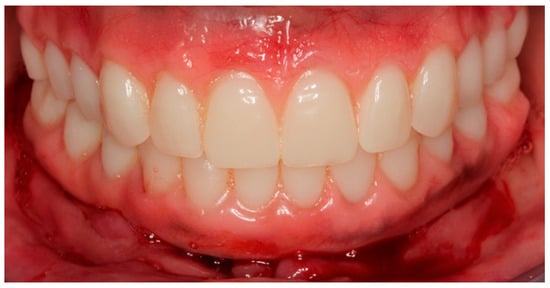

The installation and final occlusal adjustments of the full-arch rehabilitation occurred 48 h after surgery (Figure 11 and Figure 12).

Figure 11.

Occlusal view of the mandibular full-arch screw-retained rehabilitation 48 h after surgery.

Figure 12.

Buccal view of rehabilitations of both arches according to the All-on-Four concept 48 h after surgery.